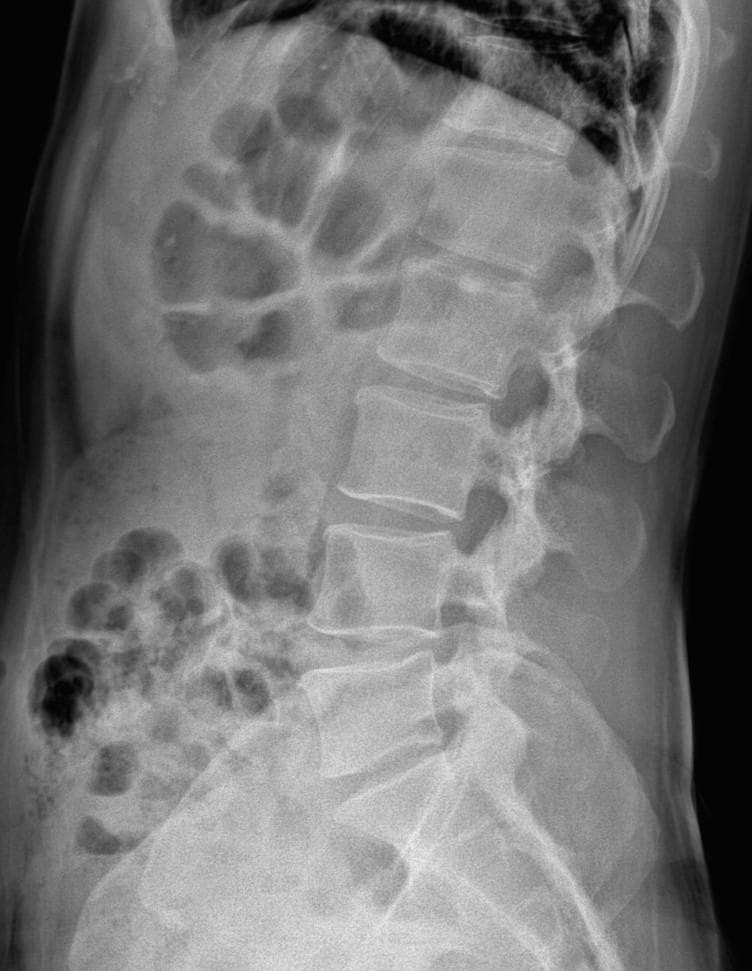

엑스레이 상에서는 요추 배열이 전반적으로 잘 유지돼 보입니다. 마나 일부 요추 간격이 좁아진 부위가 있어 보입니다. 말씀하신 것처럼 특정 동작에서 찌릿 혹은 뜨끔하거나, 최근 뻐근함이 생기는 건 디스크 초기나 근육, 인대 긴장에서도 나타날 수 있습니다.

허리의 커브가 줄어들어있다는것을 제외하고는 크게 문제가될만한 부분은없는데요 통증과불편감이 지속된다면 MRI와같은 정밀검사가 필요할수있습니다

사진상 요추 사이의 간격이 다소 좁아 보이며 간격이 좁다는 것은 퇴행성 변화를 의미하며 척추의 정렬 또한 큰 전위는 없어 보이나 허리 곡선이 정상보다는 조금 감소한 상태로 이러한 경우 근육의 긴장이나 만성적인 통증이 발생할 수 있습니다.

엑스레이 검사를 통해서는 현실적으로 뼈 위주의 평가만 가능하며 정밀하고 자세하게 평가를 내리는 것은 어렵습니다. 올리신 엑스레이 사진들에는 특별히 문제가 있다고 볼만한 소견이 크게 있어보이거나 하지는 않습니다.

우선 현재로썬 척추와 척추 사이인 디스크 공간이 좁지는 않아보이지만 다소 요추의 커브가 감소되어 있어 보입니다.